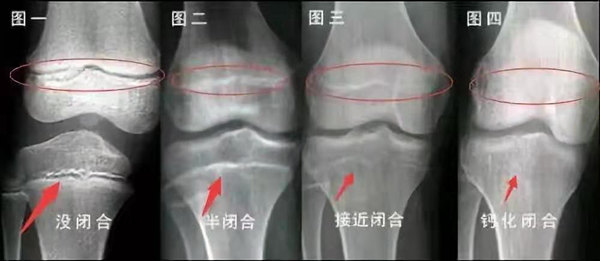

未成年時(shí)隨著年齡的增加骺軟骨端不斷骨化,骨骼就不斷增長(zhǎng)。當(dāng)骨骺線完全閉合時(shí)骨骼就停止生長(zhǎng),個(gè)子也就不再增長(zhǎng)了。一般骨骺端完全閉合的年齡是18~20歲左右。

骨骺線提前閉合最多見(jiàn)的情況是性早熟,而這也是很多醫(yī)生專(zhuān)家建議孩子進(jìn)行骨齡測(cè)量的原因之一。另外,在兒童時(shí)期大量補(bǔ)鈣也會(huì)使骨骺端提前過(guò)早閉合。

青少年一般什么時(shí)候骨骺閉合?

一般女孩是在16歲,男孩是在18歲。

一般來(lái)說(shuō),女孩的骨齡超過(guò)14歲,男孩的骨齡超過(guò)16歲,這時(shí)其骨骺線已接近閉合,基本沒(méi)有長(zhǎng)高的機(jī)會(huì)了。

因此,越早了解骨骺線閉合情況,越早干預(yù),孩子長(zhǎng)高的可能性越大。